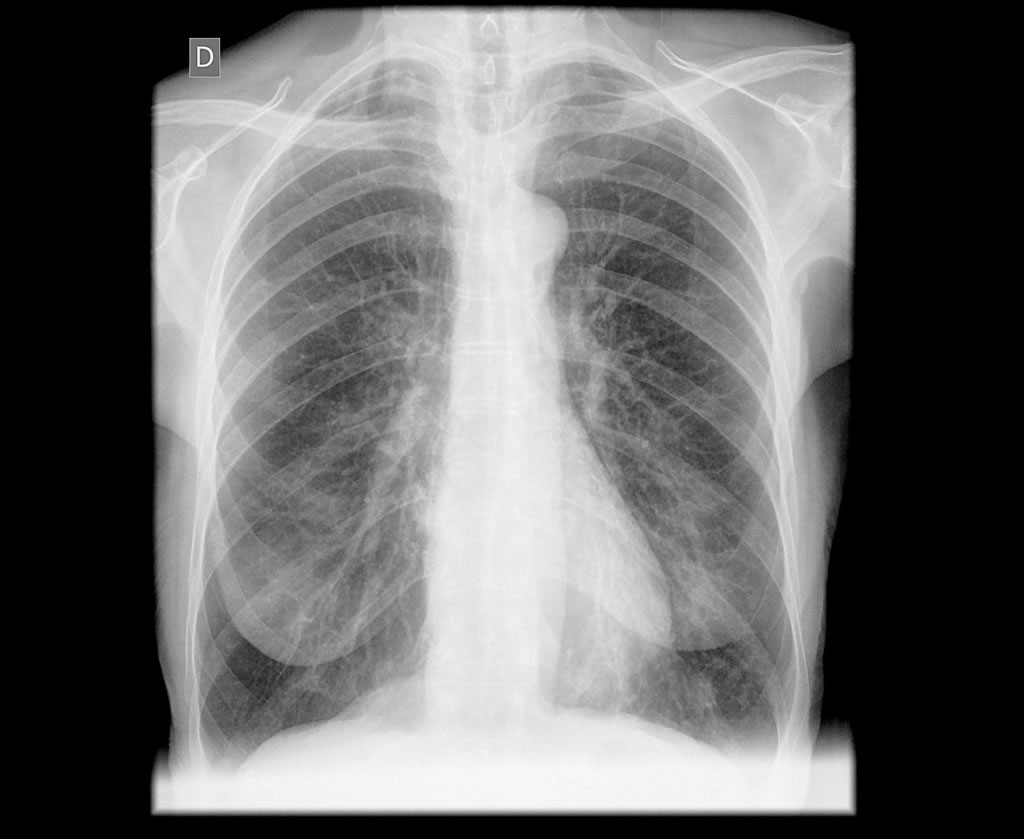

Estudio radiológico de tórax

Dentro del Programa de Control de Calidad del Centro de Imagen Diagnostica RESONA., y durante el primer semestre del año, se ha realizado un análisis de todos los estudios de tórax efectuados de junio a diciembre de 2015 en RESONA.

El análisis realizado por el Dr. César Pedrosa tiene como objetivos fundamentales la mejora de la calidad de los estudios de tórax, la búsqueda de protocolos específicos que mejoren el diagnostico de esta prueba, así como, la unificación de criterios técnicos y diagnósticos de las radiografías de tórax.